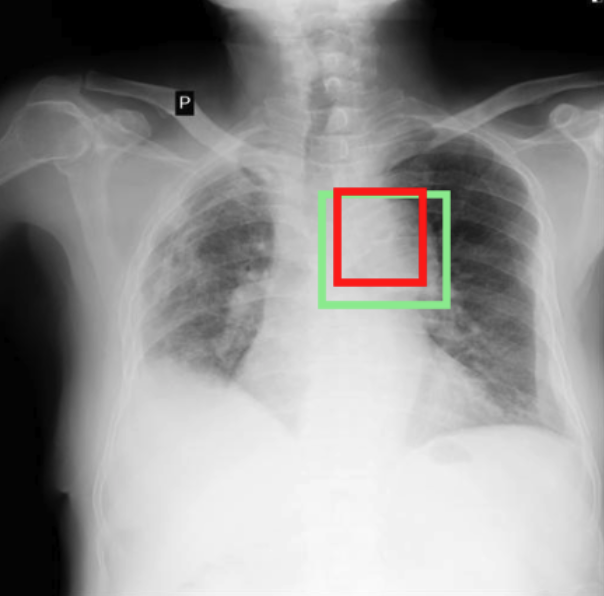

4.3.3 Visual grounding

In this section, we evaluate RadVLM’s visual grounding capabilities, which could help clinicians localize specific regions or pathologies on a CXR. This is particularly useful once a pathology has already been identified – either by a radiologist’s input or through our previously described AI tasks – since it allows one to pinpoint exactly where the abnormality appears on the image.

We report performance metrics for the three main grounding tasks RadVLM was trained on: anatomical grounding using the Chest Imagenome test set, abnormality grounding using the VinDr-CXR test set, and phrase grounding using the MS-CXR test set (Table 1). For each task, we use mean Average Precision (mAP) as our primary evaluation metric.

Our results show that RadVLM performs well at localizing anatomical regions (e.g., “right lung”, “aortic arch”, illustrated in Figure 5a), achieving a mAP of 85.8 %, by far surpassing the other CXR grounding models (Table 4). This advantage is partly explained by including the Chest Imagenome dataset (and thus the anatomical grounding task) in the training set, which CheXagent and MAIRA-2 did not leverage. However, it remains a key feature for any grounding model to possess a fine-grained understanding of CXR anatomy.

For the abnormality grounding task, RadVLM is less consistent (Figure 5b), likely due to higher sparsity of abnormality locations and labels, yet it still achieves best performance (Table 4). For the phrase grounding task, while MAIRA-2 and CheXagent demonstrate great performance, RadVLM surpasses them with a mAP of 81.8% (Table 4), presumably benefiting from the newly released PadChest-GR dataset (Castro et al.,, 2024) used for training.

Overall, these results show that our instruction tuning strategy for visual grounding (covering three essential tasks), combined to a modern VLM backbone, offers a promising avenue to help clinicians localize anatomical and pathological features during a CXR exam. Furthermore, providing fine-grained details within an LLM-generated output may also enhance the ability to answer grounded questions in a multi-turn setting, as we explore next.

a. Anatomical grounding

silhouette

junction

structures

lung

abdomen

mediastinum

arch

b. Abnormality grounding

thickening

fibrosis

enlargement

lung disease

| Anatomical grounding | Abnormality grounding | Phrase grounding | |

| CheXagent | 6.2 | 26.0 | 69.7 |

| MAIRA-2 | 19.8 | 11.3 | 80.1 |

| RadVLM | 85.8 | 34.6 | 81.8 |